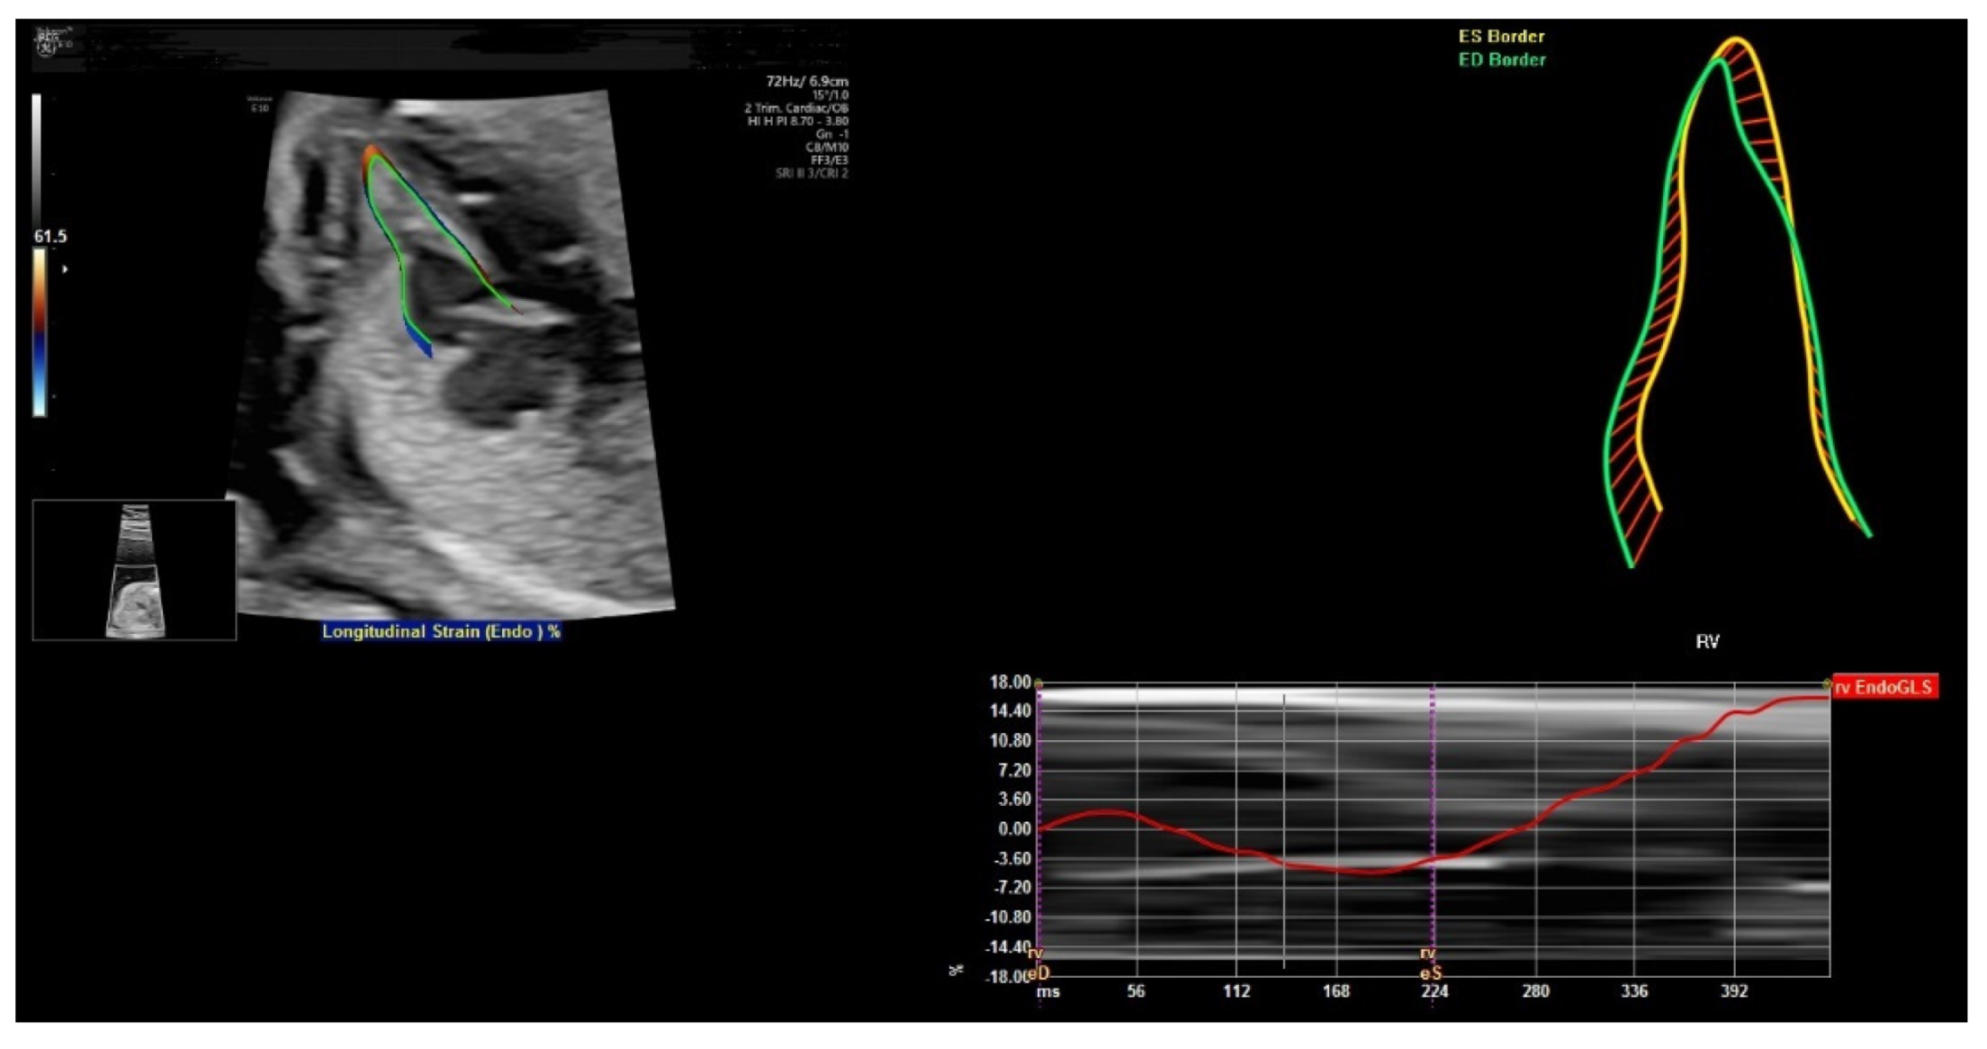

6. FetalHQ

- Van Oostrum, N.H.; Chantelle, M.; van der Woude, D.A.; Kemps, H.M.; Oei, S.G.; van Laar, J.O. Fetal strain and strain rate during pregnancy measured with speckle tracking echocardiography: A systematic review. Eur. J. Obstet. Gynecol. Reprod. Biol. 2020, 250, 178–187. [Google Scholar] [CrossRef]

- Van Oostrum, N.H.; Derks, K.; van der Woude, D.A.; Clur, S.A.; Oei, S.G.; van Laar, J.O. Two-dimensional Speckle tracking echocardiography in Fetal Growth Restriction: A systematic review. Eur. J. Obstet. Gynecol. Reprod. Biol. 2020, 254, 87–94. [Google Scholar] [CrossRef]